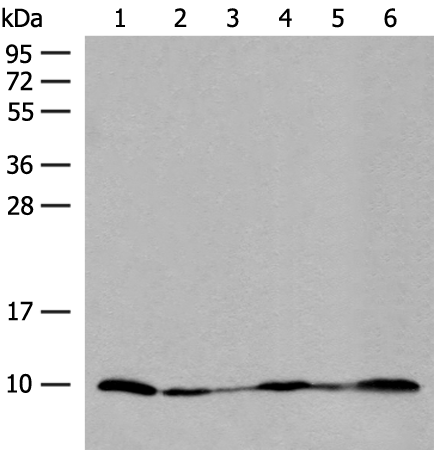

分类: 科研抗体货号: P06607别名: MTGM; MTGMP; C20orf52; bA353C18.2应用: WB,IHC反应种属: Human, Mouse